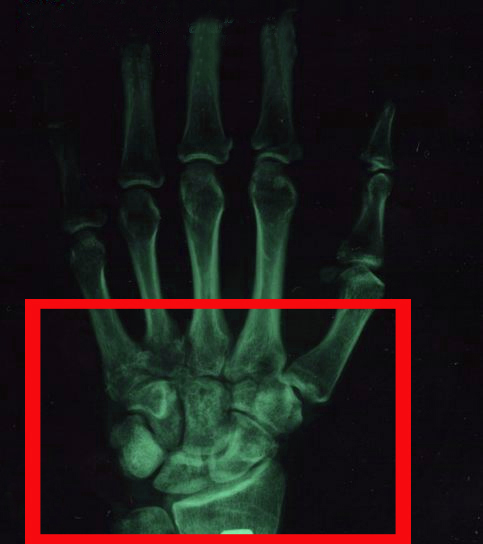

Впрочем, даже если вы имеете полный набор этих симптомов, это по-прежнему не является основанием для постановки окончательного диагноза, поэтому диагностику всегда должен проводить доктор используя рентгеновский снимок.

Лечение перелома костей запястья начинается с диагностики перелома. Чтобы идентифицировать эту травму используют следующие методы диагностики:

- Для локализации травмы и подтверждения степени тяжести перелома делается рентгенография.